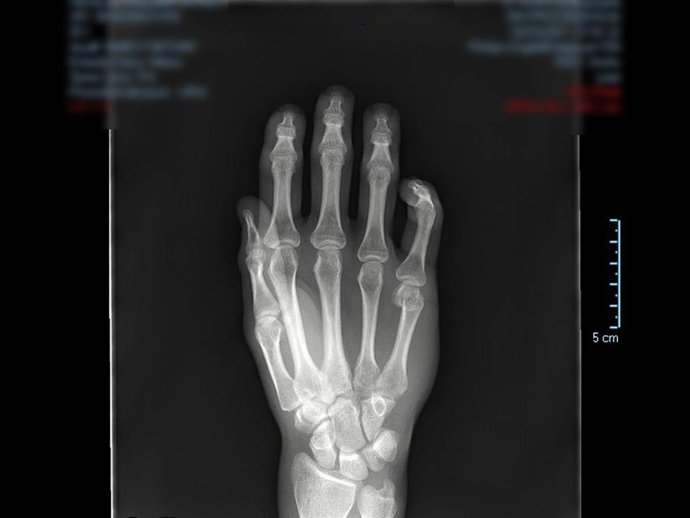

Radiografía de una mano

Radiografía de una mano - QUIRÓNSALUD MARBELLA